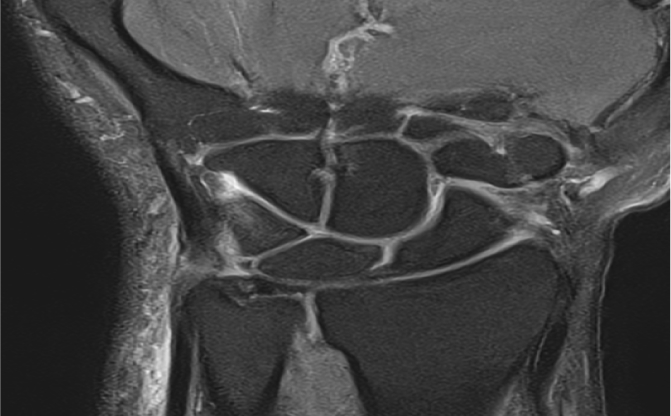

손목의 자측(새끼손가락 쪽)에 위치한 연골복합체(TFCC)는

손목의 안정성을 유지하고 충격을 흡수하는 중요한 구조물입니다.

진단장비로 정확한 상태 진단